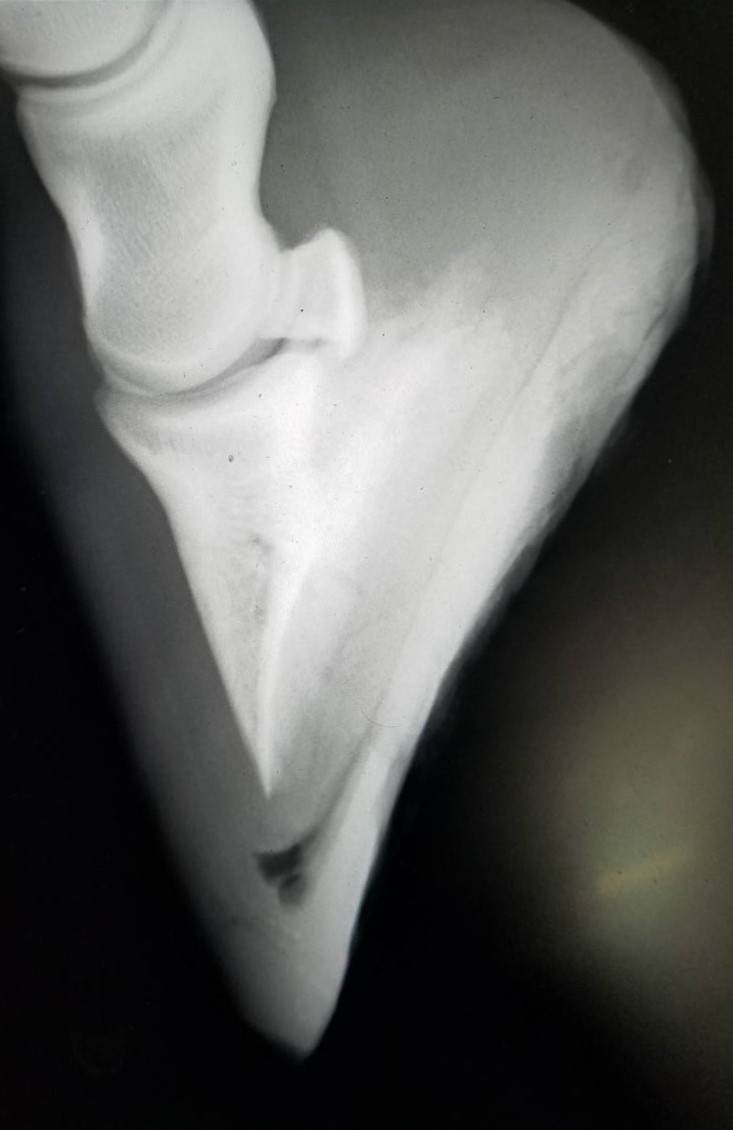

6月9日に左前脚を挫跖し、いったんは回復したものの、6月18日に再び左前の歩様が悪くなりました。調べたところ、蹄内にフレグモーネの症状が見られ、発熱し、白血球の数値も上がっていました。再度の挫跖か、蹄から菌が入ったものと考えられます。その後、熱と白血球の数値は落ち着きましたが、しばらくは左前脚を地面につけるのを嫌がるほど痛がっていました。6月28日のレントゲン検査の結果、中に溜まった膿が抜ける部分がなく、蹄骨の下を通って蹄球から抜けるという珍しい症例でした。そのため、膿が通り抜けた部分が空洞になって蹄底が上下に動く形になり、古い蹄の部分が当たり痛みが出ていたものと推測されます。

現在はACS(アドバンスクッションサポート)を蹄底に充填し、空洞を押さえつけるような形にしていることから、痛みはなく、歩様も正常です。今後は特に治療の必要はなく、蹄が伸びて、蹄の中の状態が改善されるのを待つだけという状況です。獣医師、装蹄師の診断では、蹄鉄を履かせて乗り出すまでに至るには1ヶ月程度必要とのことです。